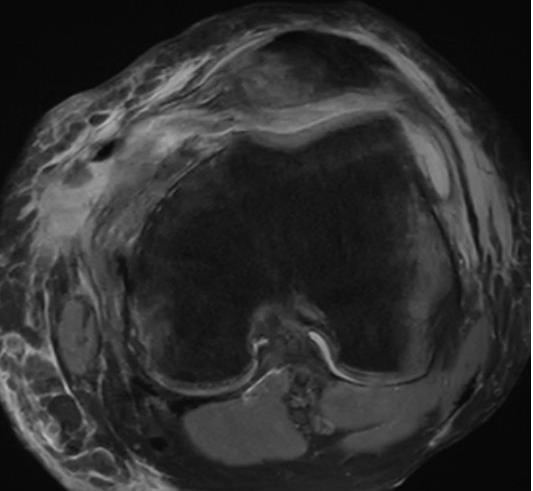

内侧髌骨韧带关节镜下重建后,术中在关节镜下观察,髌骨已经复位良好,术后MRI影像学表现如下:

术前髌骨半脱位状态            术后髌骨复位